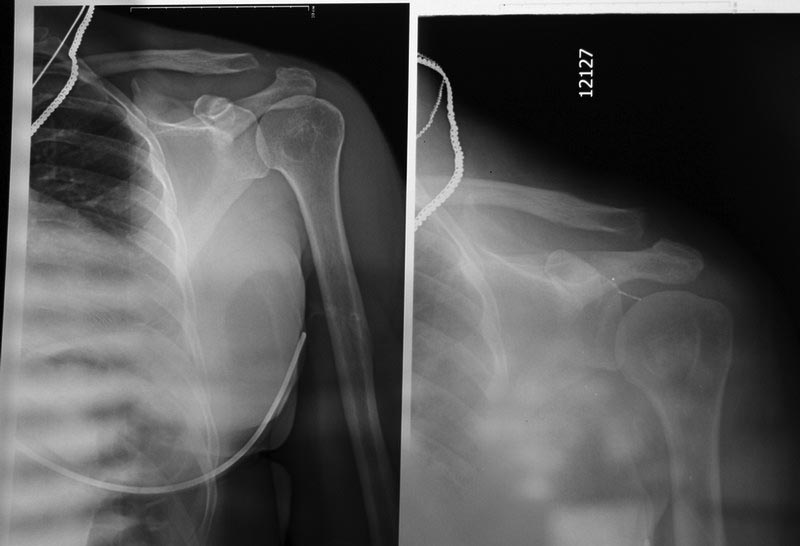

Есть ли показания для оперативного вмешательства у женщины с застарелым разрывом АКС? Женщина обратилась с жалобами на боль в области плечевого сустава на протяжении 4,5 месяцев после травмы. Боль беспокоит при подъеме руки от 45 град до 90. Также беспокоит онемение 3- 4 пальца кисти, периодически возникающий отек кисти. В сентябре после травмы диагностирован разрыв АКС слева Tossy 1, была наложена повязка Дезо. Затем периодически получала разные виды физиотерапии, мази без эффекта.Был проведен повторный Rg. На УЗИ я выявила расширение АКС до 15 мм, (на здоровой стороне суставная щель до 5 мм), содержимое неоднородное, имеется неровность дистального конца ключицы. Признаки разрыва акромиально-ключичной связки. Целостность сухожилий ротаторной манжетки сохранена. Выпота в сумках нет.Описание Рентгенолога: 1ый снимок октябрьский , второй справа -середина февраля (недавно). 1 ый снимок сделан с грузом - второй - без груза. На рентгенограмме левой плечевой кости с плечевым суставом с центрацией на левый АКС от февраля года в сравнении с рентгенограммой от октября отмечается разрыв КАС первой степени по Tossy, в динамике расстояние левого КАС с 0,7 мм и ступенеобразной деформацией увеличилась до 1,1 см (я не опечаталась - такова размерность в заключении) с признаками лизирования эпифиза левой ключицы, реакция мягкотканного компонента отсутствует.Подскажите, пожалуйста, какая же здесь степень разрыва по Tossy? Необходимо ли оперативное вмешательство, по поводу данного разрыва? Считаете ли Вы, что есть разрыв связки? Какова дальнейшая тактика ведения пациентки.

На мой взгляд впервую очередь необходимо исключить повреждение сухожилий ротаторной манжеты. Выполнение лишь только УЗИ не дает ответ. Поэтому выполните МРТ плечевого сустава, с акцентом на сухожилия. По рентгенограммах повреждение КАС не критическое -1 степени, но такую клинику довать не может. Ко всему этому необходимо исключить шейные дела (остеоходроз и т.д.)

В механизме данного повреждения не исключается, а скорее присутствует повреждение плечевого сплетения..Сделать ЭНМГ. Для оценки данной травмы лучше использовать классификацию АО/ASIF. В данном случае я бу поставил степень 4 возможно имеется повреждение места прикрепления передней порции дельтовидной мышцы. Учитывая это малоинвазивная операция будет несостоятельной. Возможное решение: металодез huck-plate c обязательной ревизией и восстановлением дельтовидной мышцы, ауто или ксенопластика связок.

На Rg не исключается внутрикостное образование головки и шейки плечевой кости. Сделайте КТ.